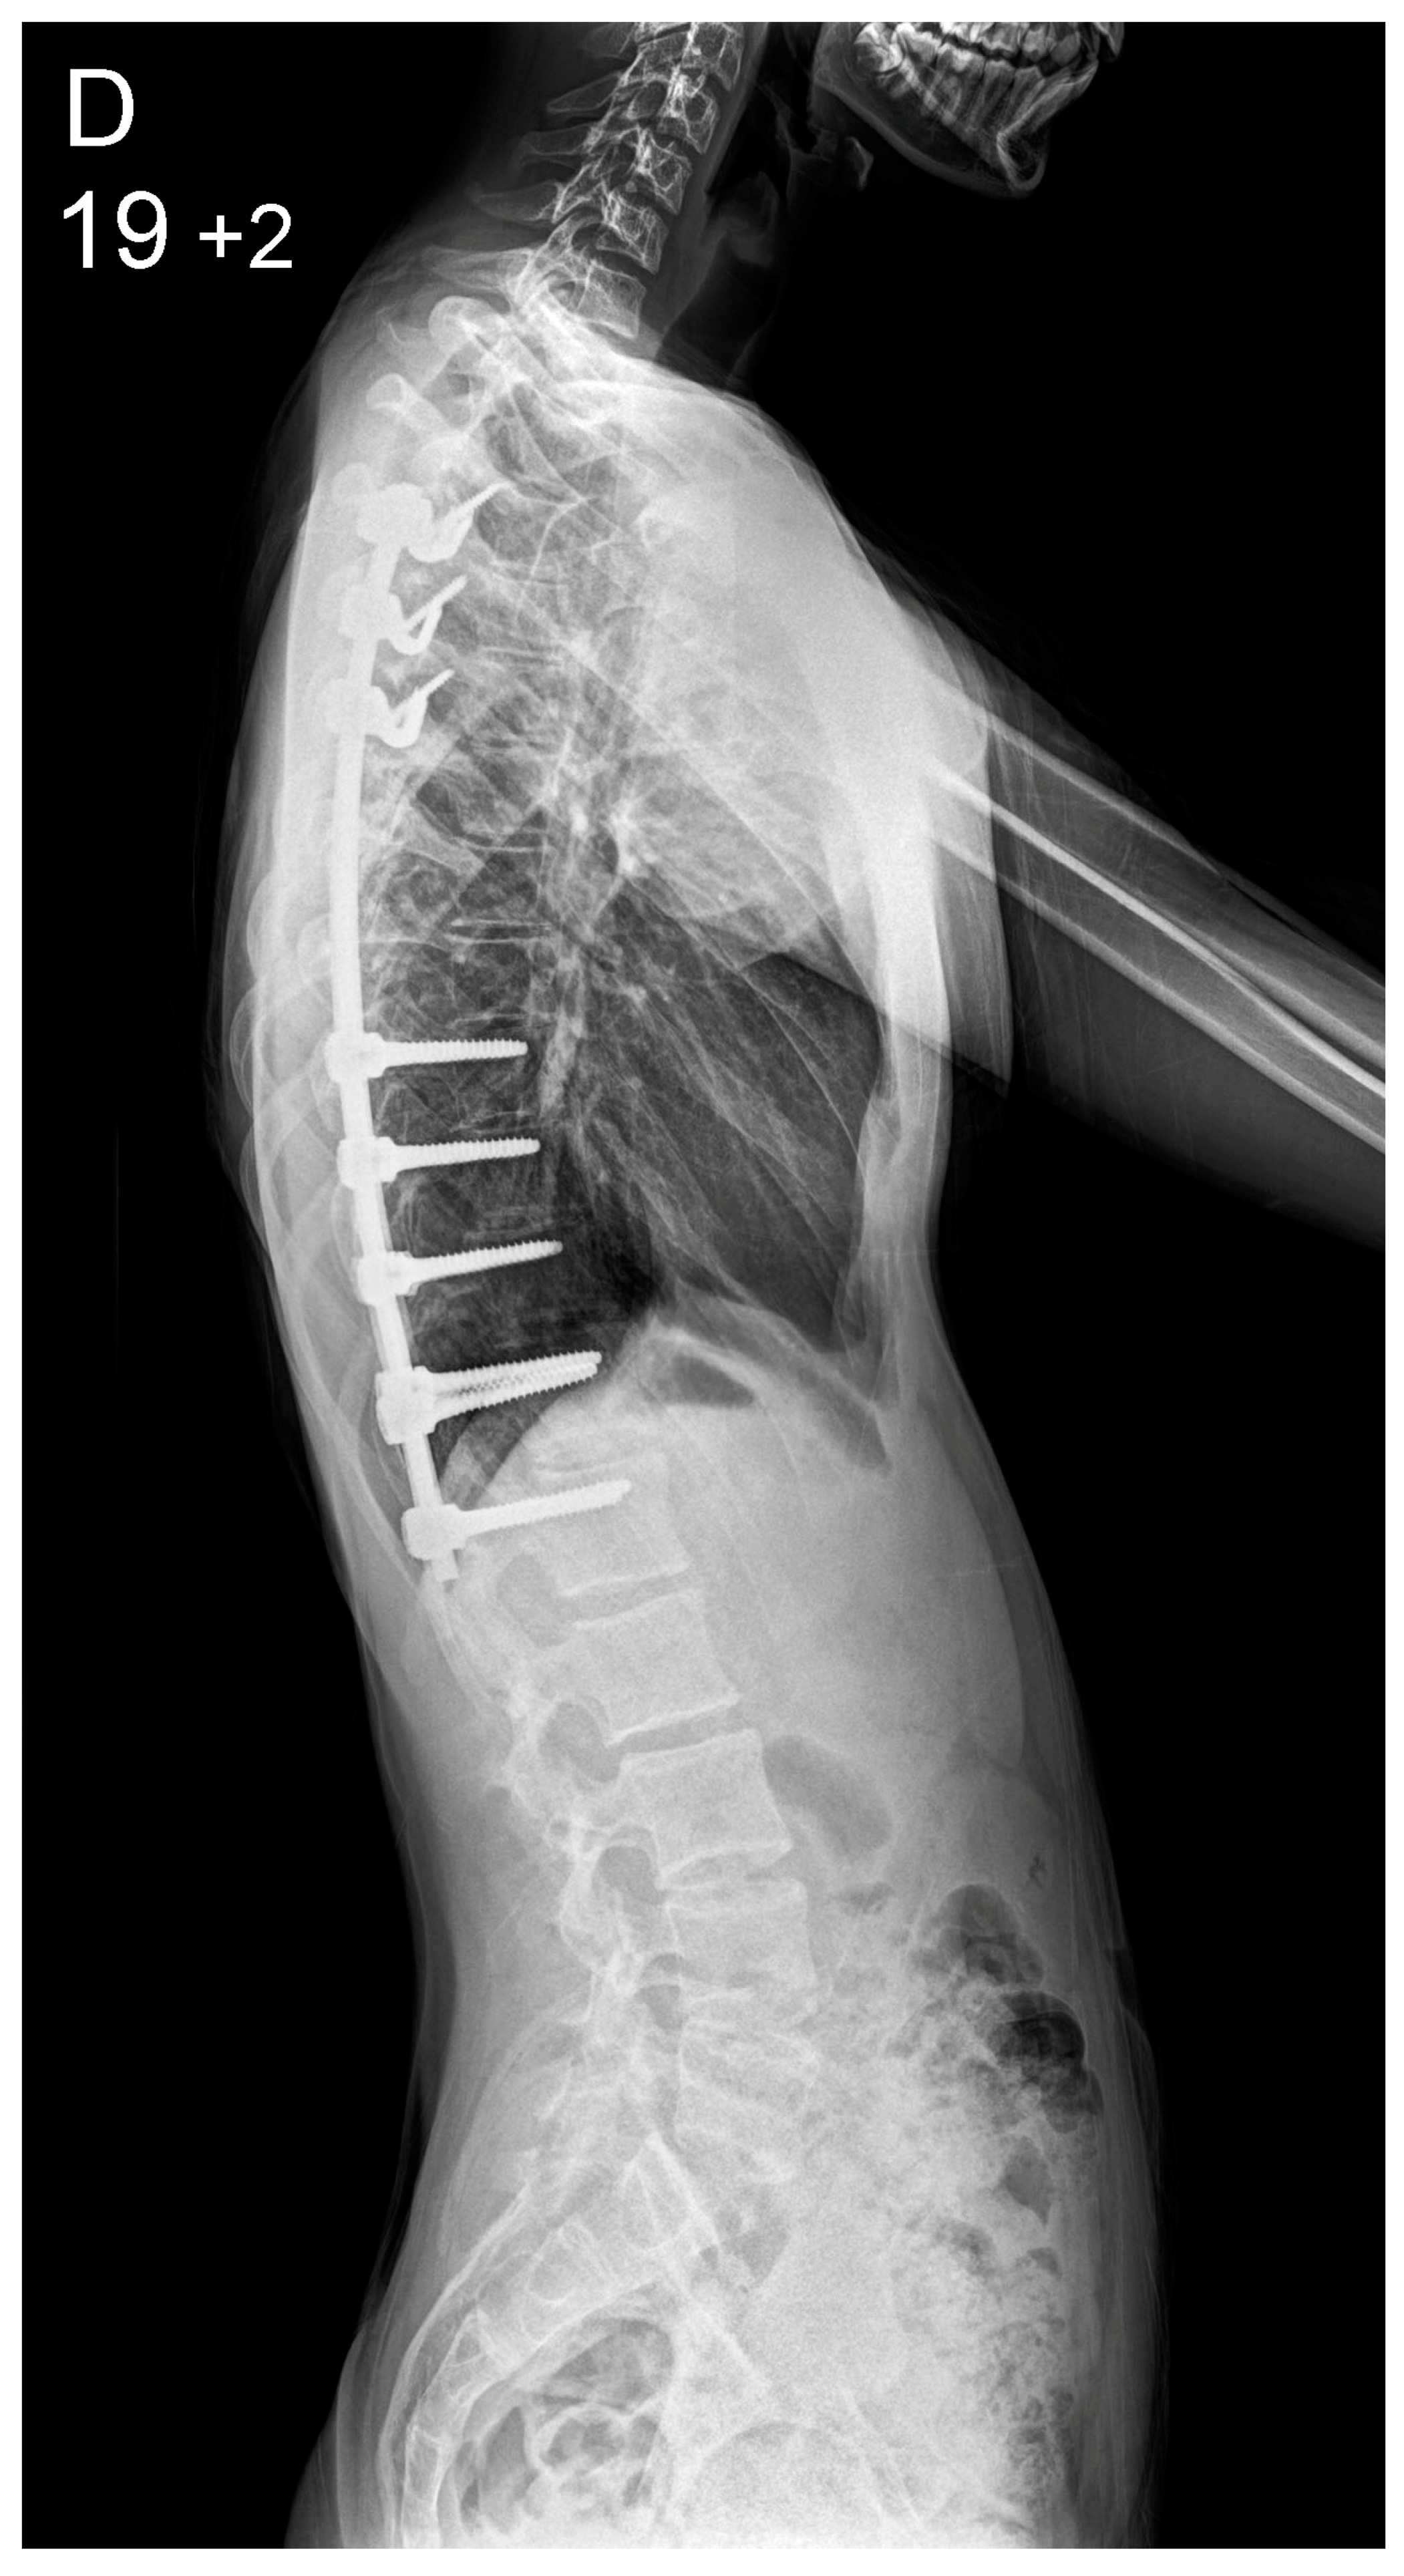

| Thoracic Kyphosis | |||

| Preoperative (°) | 38 (3–80) | 31 (−17–65) | 0.01 * |

| Postoperative (°) | 42 (16–62) | 43 (30–58) | 0.2 |

| Correction Index (%) | 10 (38–92) | 31 (34–149) | <0.001 * |

| Lumbar Lordosis | |||

| Preoperative (°) | 55 (28–84) | 53 (21–90) | 0.33 |

| Postoperative (°) | 47 (25–68) | 45 (29–62) | 0.11 |

| Correction Index (%) | 18% (0–42) | 20% (0–44) | 0.64 |